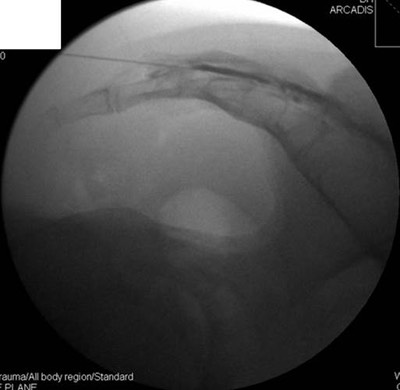

Using a specialised X-ray machine called a fluoroscope, the needle is placed using X-ray guidance. Correct needle placement is confirmed using radiological dye called ‘contrast’, usually Omnipaque 240. This improves the effectiveness and safety of the injection.

Examples of joint injections requiring fluoroscopy include:-

Shoulder (Gleno-humeral Joint ‘GHJ’)